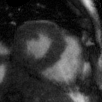

Supervised Deep-Learning (DL)-based reconstruction algorithms have shown state-of-the-art results for highly-undersampled dynamic Magnetic Resonance Imaging (MRI) reconstruction. However, the requirement of excessive high-quality ground-truth data hinders their applications due to the generalization problem. Recently, Implicit Neural Representation (INR) has appeared as a powerful DL-based tool for solving the inverse problem by characterizing the attributes of a signal as a continuous function of corresponding coordinates in an unsupervised manner. In this work, we proposed an INR-based method to improve dynamic MRI reconstruction from highly undersampled k-space data, which only takes spatiotemporal coordinates as inputs. Specifically, the proposed INR represents the dynamic MRI images as an implicit function and encodes them into neural networks. The weights of the network are learned from sparsely-acquired (k, t)-space data itself only, without external training datasets or prior images. Benefiting from the strong implicit continuity regularization of INR together with explicit regularization for low-rankness and sparsity, our proposed method outperforms the compared scan-specific methods at various acceleration factors. E.g., experiments on retrospective cardiac cine datasets show an improvement of 5.5 ~ 7.1 dB in PSNR for extremely high accelerations (up to 41.6-fold). The high-quality and inner continuity of the images provided by INR has great potential to further improve the spatiotemporal resolution of dynamic MRI, without the need of any training data.

翻译:在这项工作中,我们建议了一种基于IRI的方法,用这种方法来改进动态磁共振感应成像(MRI)重建,而该方法只是以高度低劣的 k-空间数据为基础,而该数据仅以磁共振坐标作为投入。具体地说,拟议的IRI将动态MRI图像作为一种隐含功能来表示,并将其编码到神经网络中。网络的权重仅从稀有的(k, t)空间数据本身中学习,而没有外部培训数据集或先前的图像。 利用基于IRI的强有力隐含性稳定化,同时不以清晰的动态和时空坐标坐标坐标坐标坐标作为投入。 拟议的IRIR将动态MRI图像作为一种隐含功能,将其编码到神经网络中。网络的权重仅从淡化的(k, t)空间数据本身学习,而没有外部培训数据集或先前的图像。